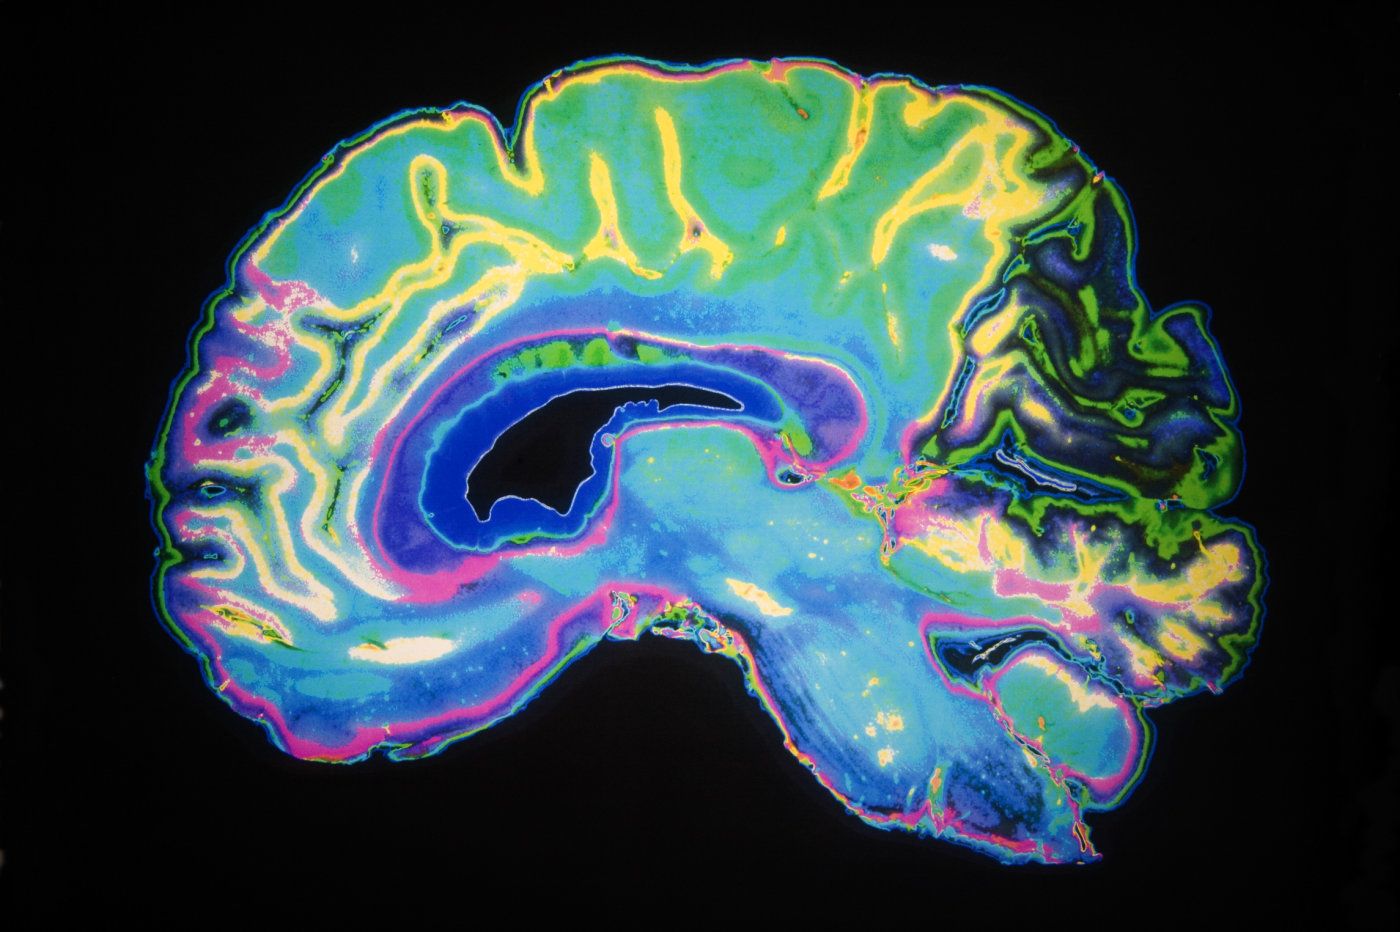

Identifican las neuronas que procesan emociones

Las emociones de los eres humanos han llamado desde tiempos inmemorables la atención de los científicos y especialistas que han dedicado años a su estudio. Y ahora, una reciente investigación el Instituto Tecnológico de Massachusetts, parece haber podido identificar de forma exacta cuáles son las neuronas que provocan, o al menos procesan, todas las emociones que los … Leer más Identifican las neuronas que procesan emociones